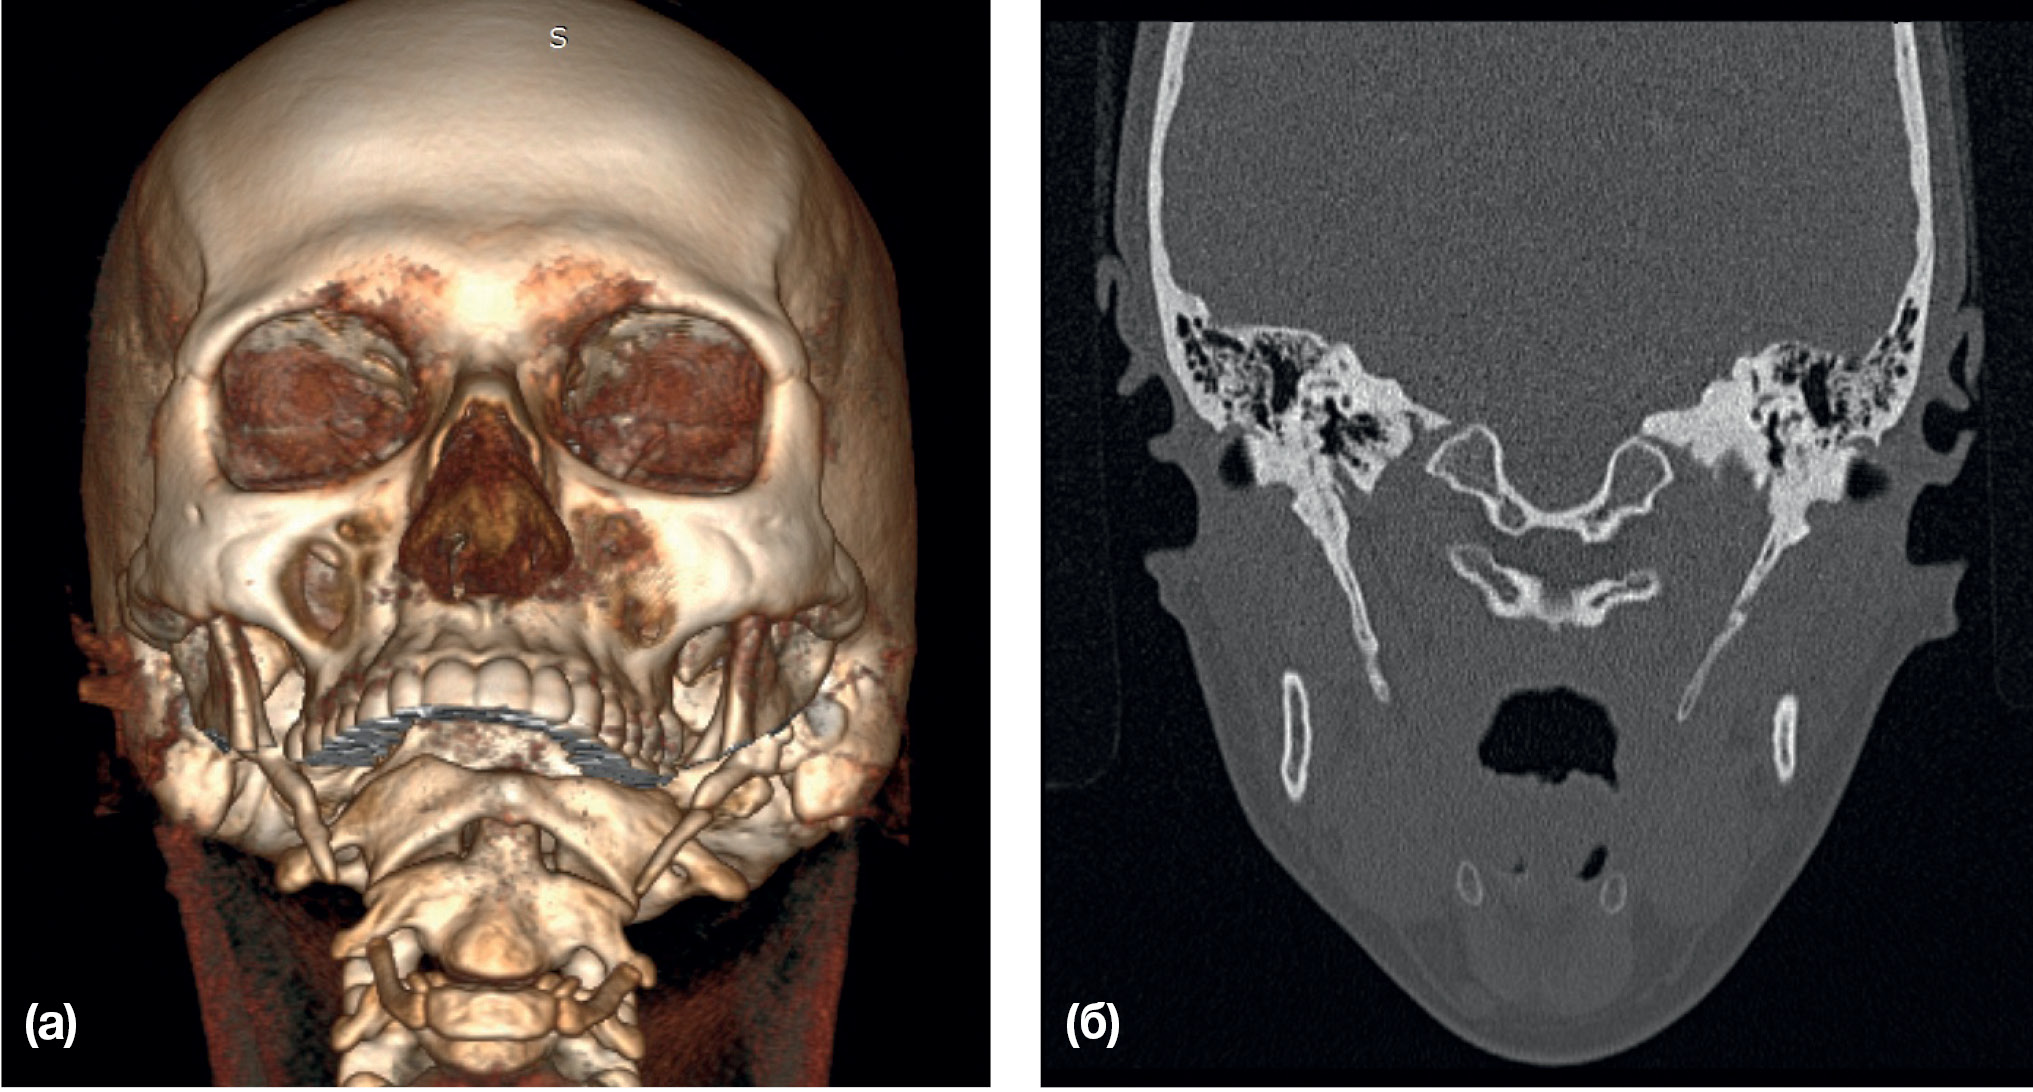

Рис. 3. Контрольные снимки после удаления шиловидных отростков

Примечание. (а) — 3D-реконструкция, вид справа; (б) — 3D-реконструкция, вид слева.

Рис. 6. Контрольные снимки после удаления шиловидных отростков